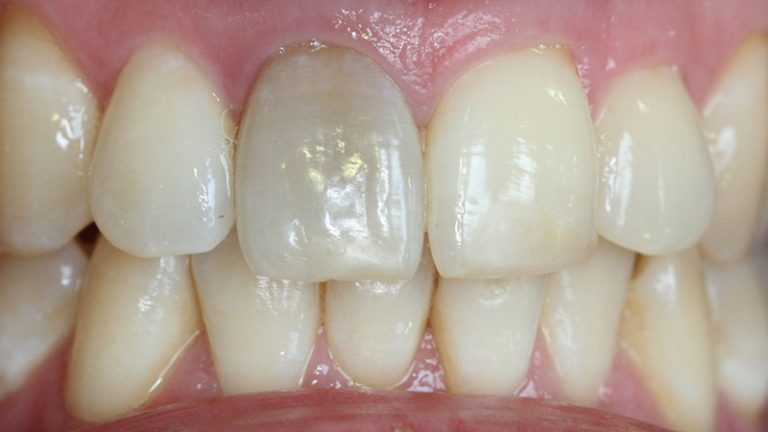

Para saber se o seu dente morreu, antes de ir ao consultório odontológico, claro, você deve prestar atenção na cor dele. Geralmente, quando o nervo morre, acontece o escurecimento dental. O dente também fica dolorido quando é tocado e pode até surgir uma fístula na gengiva, com saída de pus.